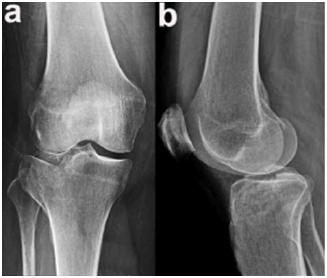

Enunciado 4335215-1

O exame apresentado indica o envolvimento do platô tibial

Enunciado 4335217-1

Assinale a alternativa que indica os princípios a serem seguidos na osteossíntese do platô tibial lateral, nesse caso.

Enunciado 4335216-1

No acesso cirúrgico para o caso, deve-se abordar a articulação do joelho através do espaço entre os músculos

Enunciado 4335218-1

Enunciado 4335218-2

A abordagem cirúrgica para a osteossíntese foi realizada pela via

Enunciado 4335219-1

A estrutura que mais corre risco de ser lesada nessa abordagem é o